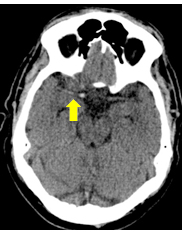

A non-contrasted CT scan of the brain is ordered for the patient. Results are shown in Figure 1.

Figure 1. Non-contrasted CT brain scan of the patient.

A hyperdense artery sign is a finding that can be seen quickly on non-contrasted CT brain scans without performing angiography (Figure 2). This sign has been shown to be up to 95% specific and 52% sensitive for detecting intraluminal thrombus and, therefore, arterial occlusion.4

Figure 2. The yellow arrow points to the hyperdense artery sign at the terminus of the right internal carotid artery and extended into the middle cerebral artery on the patient’s non-contrasted CT brain scan (Figure 1).